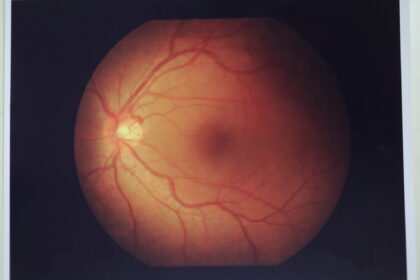

眼底検査

眼底の状態を確認する検査です。瞳孔を開く散瞳薬を点眼し、眼底鏡で状態を観察します。